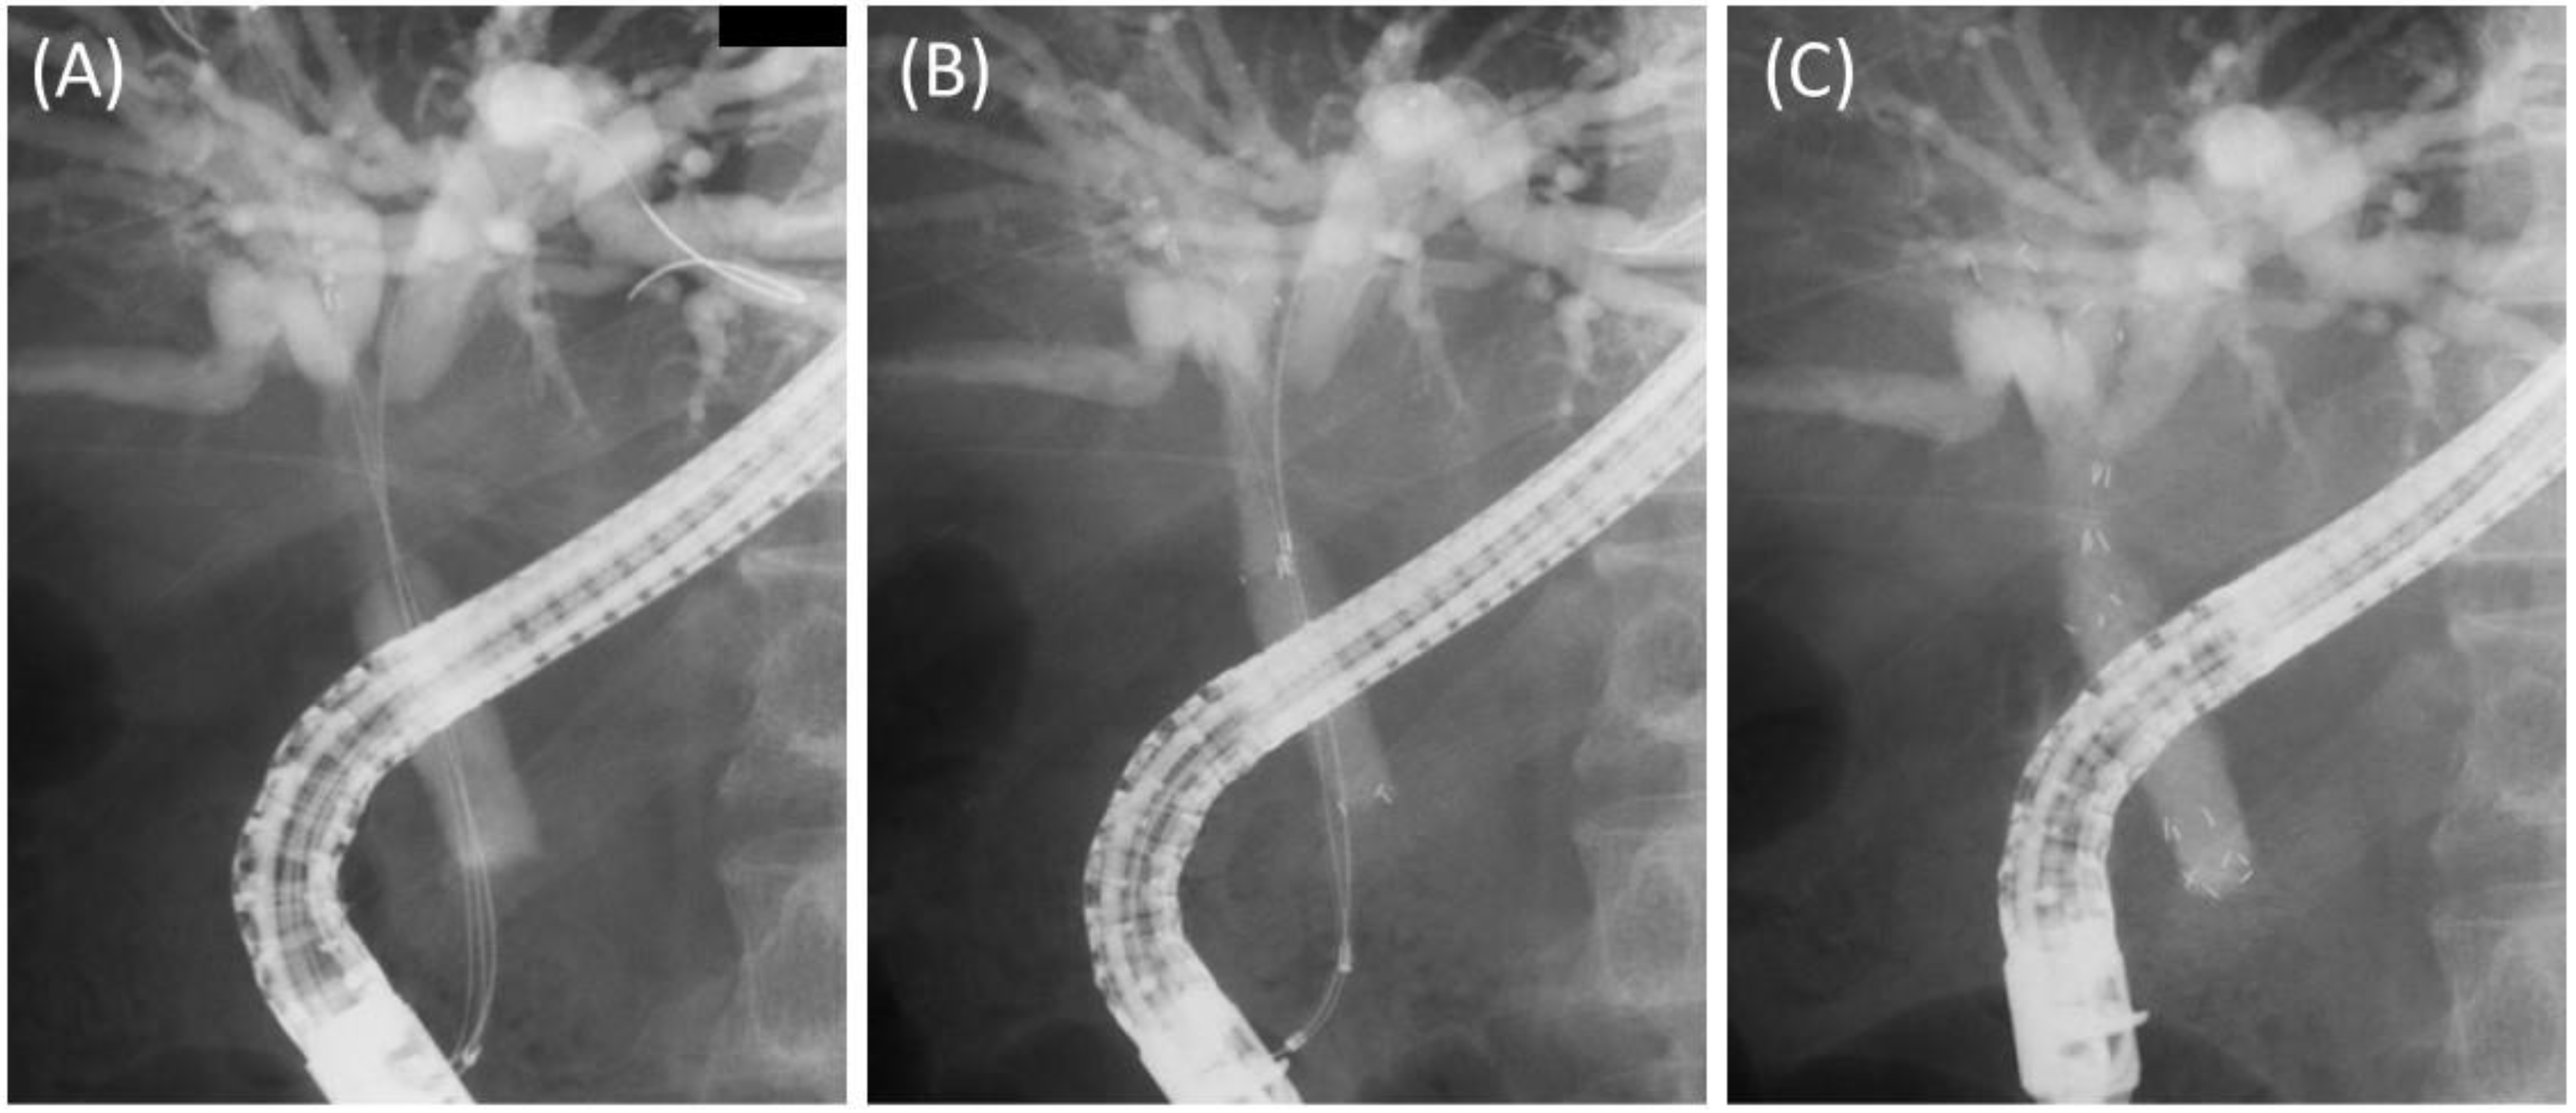

1. Introduction

2. Patients and Methods

2.2. Procedures

3.2. Details and Outcomes of the Procedures